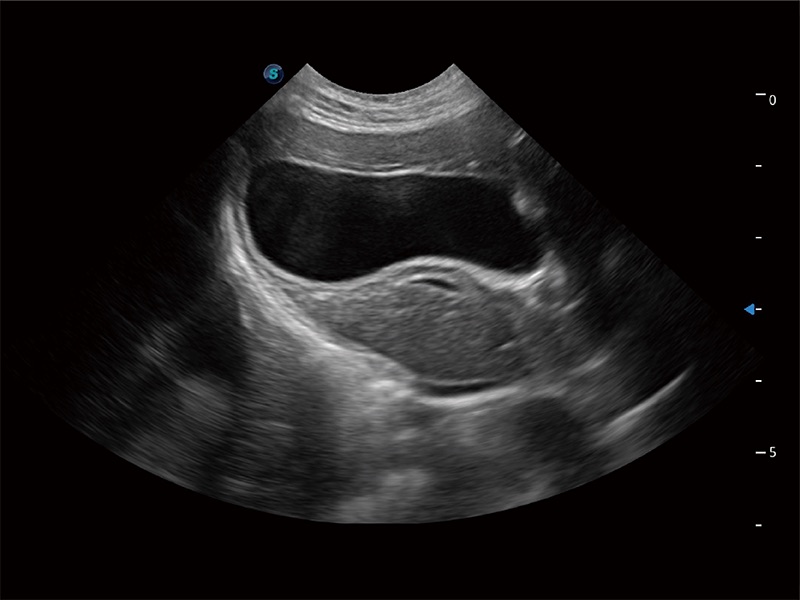

动物是人类最亲密的朋友和最值得信赖的伙伴。环球UG官网也一直致力于探索动物专用的超声影像解决方案。全新推出的ProPet系列,是环球UG官网在动物超声影像智能化、专业化、精准化的一次跨越式革新。动物不能用言语来表述自己的不适,通过超声影像,ProPet系列搭建了动物医生与不同物种沟通的“桥梁”,为动物医生注入了“治愈之力”。 ProPet 80 是环球UG官网匠心打造的一款高端动物专用彩超,采用性能卓越的全新硬件架构,极大提升超声系统的运行效率和数据处理能力,帮助动物医生从容应对日益增多的挑战性病例和日益多样化的临床需求。

高性能和先进的临床应用工具可以为动物医生提供临床信心。ProPet 80 搭载了先进的腹部和浅表应用工具,帮助医生在日常临床实践中发挥前所未有的作用。

一键自动识别膀胱壁及自动测量膀胱容积,不受膀胱形状和大小的限制,帮助医生快速精准获得测量的数据。